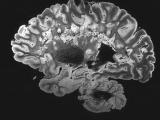

Рак легких распространяется на мозг примерно у четверти пациентов с запущенной формой заболевания...